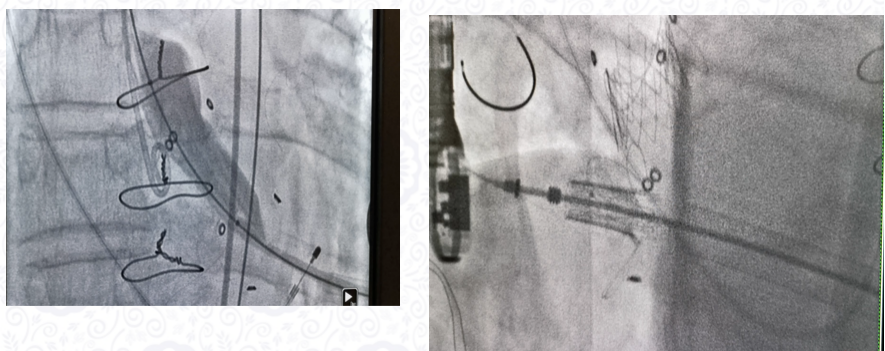

张海波教授报告了国内外主动脉瓣生物瓣毁损介入技术的发展历程,2002年Cribier教授成功完成国际首例TAVI手术开始,2008年首例主动脉瓣生物瓣的瓣中瓣介入手术,2017年美国FDA正式批准主动脉瓣和二尖瓣的瓣中瓣介入手术技术的适应症。并汇报了主动脉瓣、二尖瓣双瓣毁损的双瓣微创介入瓣中瓣手术效果。术前双瓣要经过三维CT扫描,评估两个瓣架支架的夹角和距离,虚拟植入介入瓣膜后的介入瓣支架要评估是否互相干扰等风险。另外还汇报了安贞医院心外科瓣膜中心团队主动脉瓣生物瓣需要同期打断瓣环再植入介入瓣的经验,总结了术中定位常见的问题和防治策略。朱俊明、郭惠明、李岩等教授讨论了主动脉瓣生物瓣瓣环球囊打断的风险和技术细节问题。

安贞医院张海波教授团队报告的主动脉瓣、二尖瓣双瓣生物瓣毁损,主动脉瓣fracture技术打断瓣环的双瓣微创介入瓣中瓣手术技术